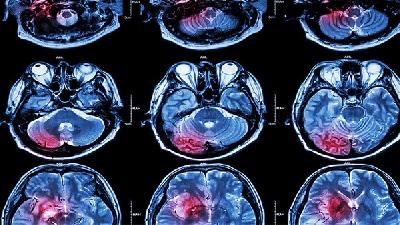

震颤型脑瘫多由锥体外系损伤及小脑损伤引起,其严重的影响着患者的身心健康,震颤型脑瘫是脑瘫常见类型之一,会导致震颤型脑瘫患者肌肉控制失调引起的身体运动困难和体位困难,严重的影响了患者的生活自理能力,所以震颤型脑瘫的治疗是非常有必要的。那么,男子震颤型脑瘫饮食方面需要注意什么呢?最近有越来越多的证据证实,饮食结构是震颤型脑瘫的一大重要因素。实验室研究结果显示,震...